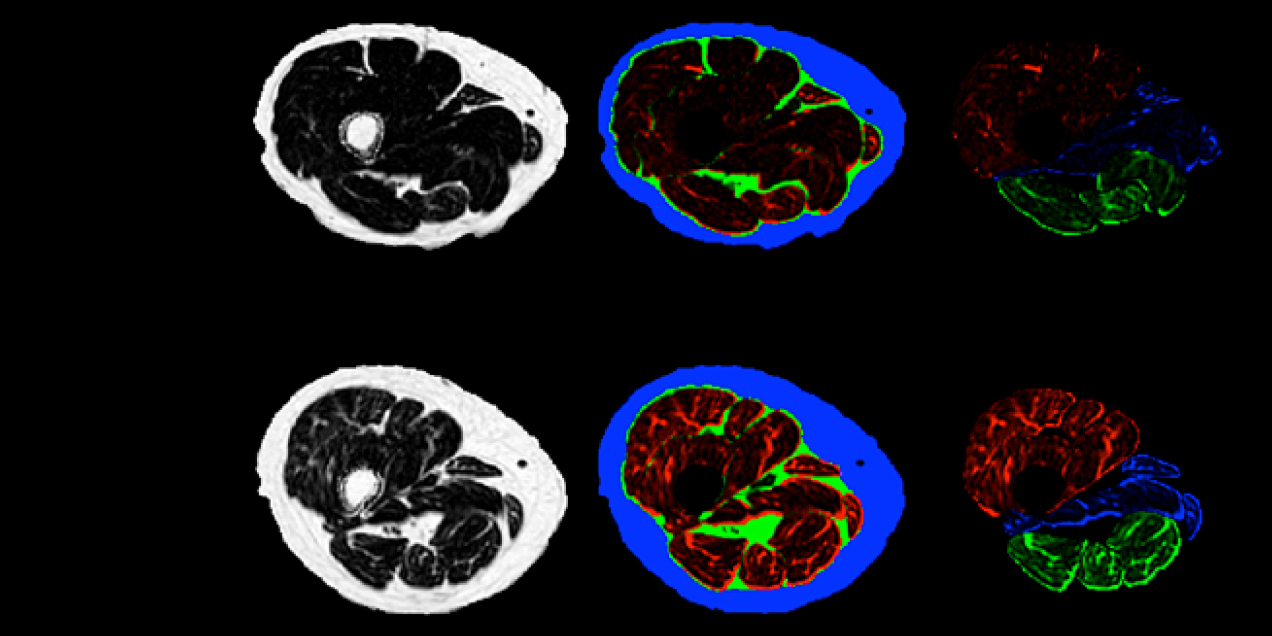

This study uses advanced MRI to assess thigh muscle fat and size in people with knee osteoarthritis and how these changes relate to cartilage damage, muscle function, and symptoms.